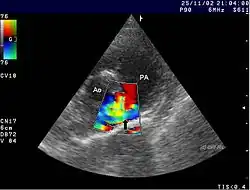

Ein persistierender oder offener Ductus arteriosus Botalli (Ductus arteriosus persistens, persistierender Ductus arteriosus, PDA) liegt vor, wenn sich der Ductus arteriosus, der im fetalen (vorgeburtlichen) Blutkreislauf eine Verbindung zwischen Aorta (der Hauptschlagader) und Truncus pulmonalis (Lungenarterie) herstellt, drei Monate nach der Geburt noch nicht verschlossen hat. Er schließt sich normalerweise in den ersten Lebenstagen. Der persistierende Ductus arteriosus zählt zu den angeborenen Herzfehlern.